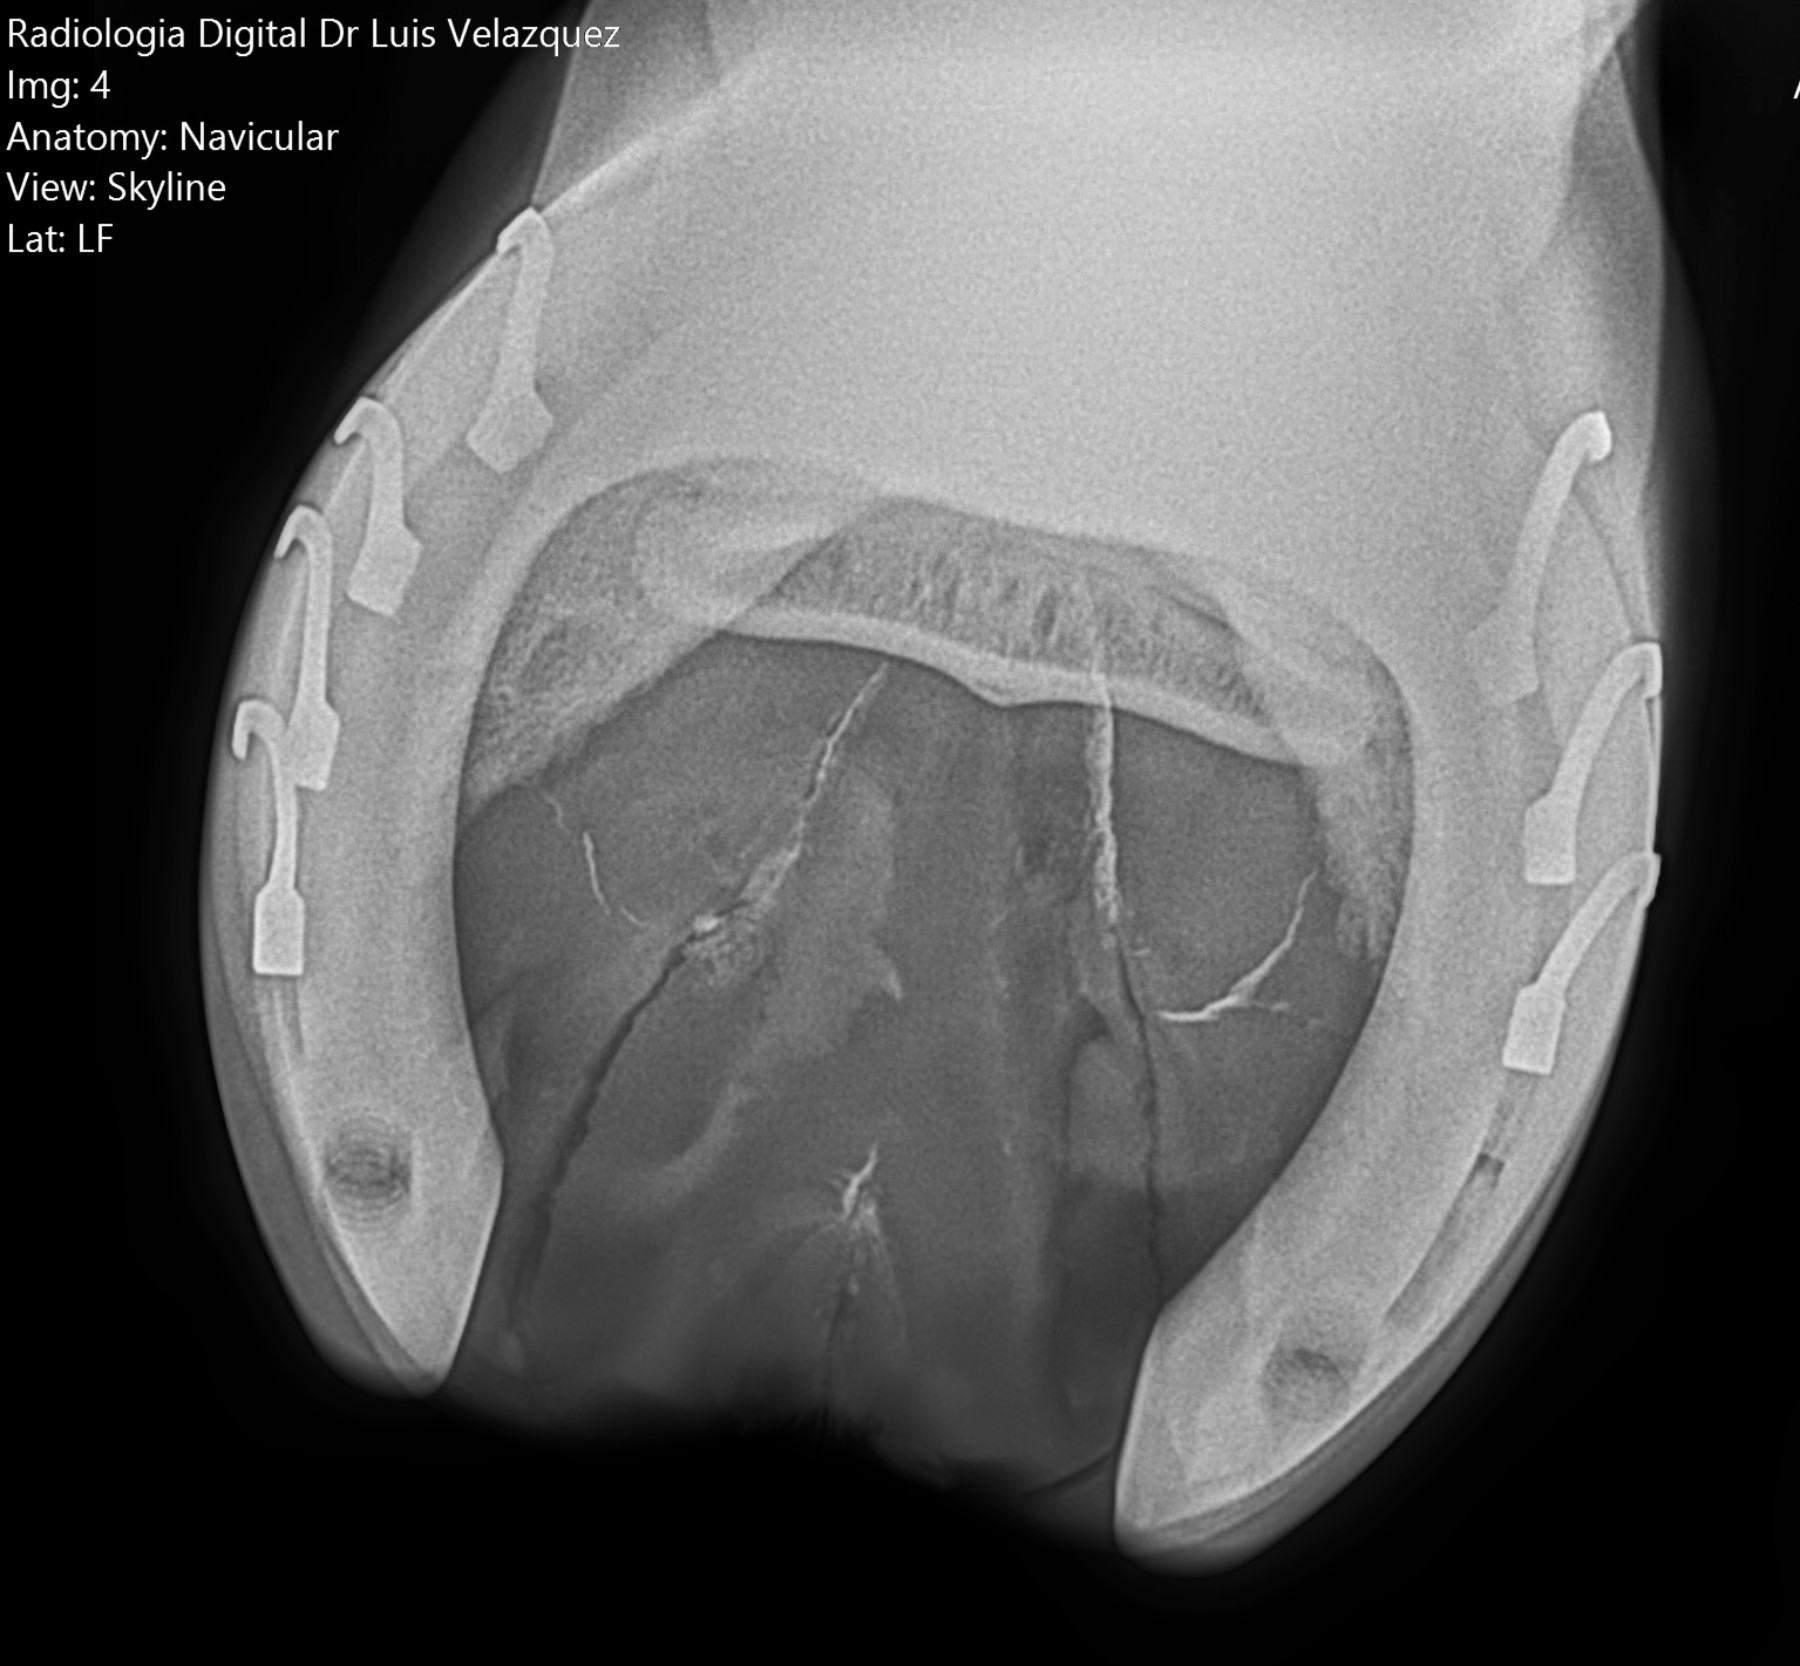

Radiología Digital como Herramienta Complementaria en el Dictamen de Bienes Muebles